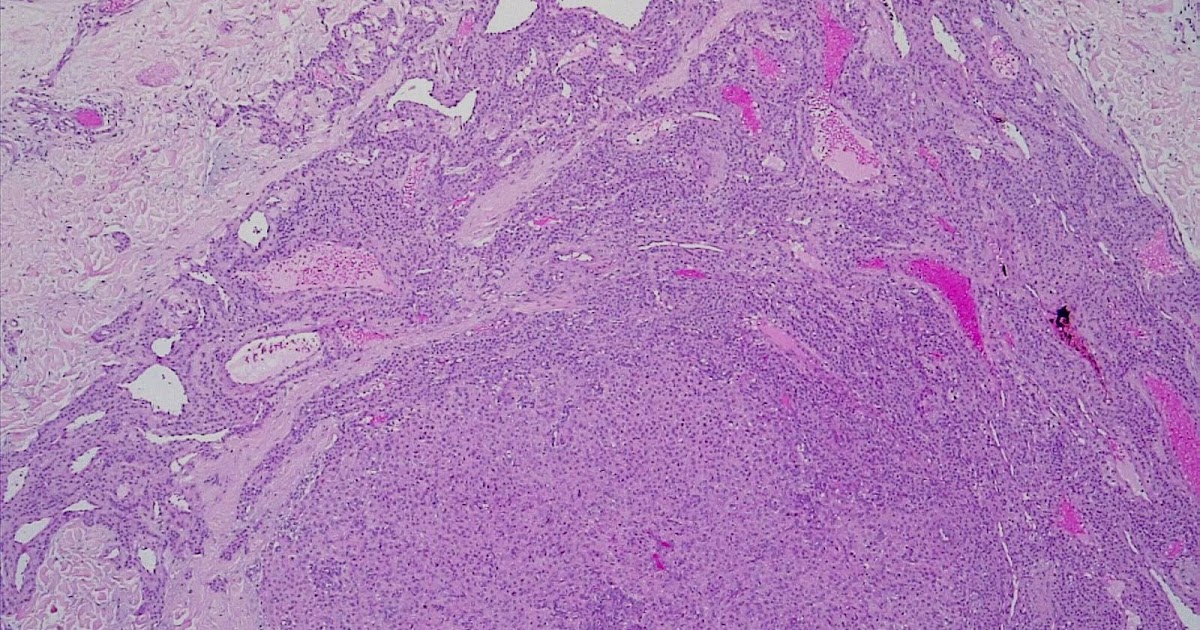

Patologia B: NEOPLASIAS RENALES 😈

Carcinoma de células renales bilateral y oncocitomatosis renal sincrónicos 😈